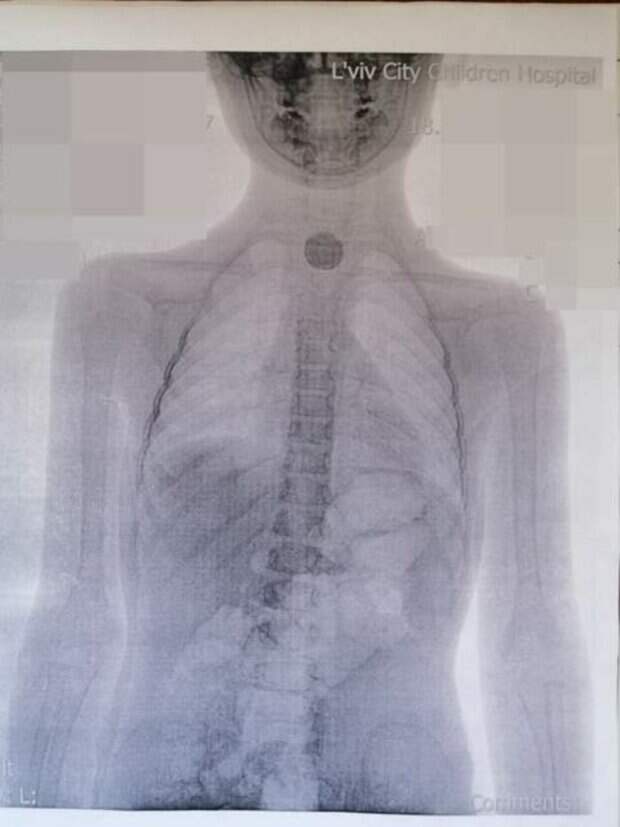

На Львовщине 5-летняя девочка проглотила батарейку Инцидент произошел 10 июля. Сначала ребенок призналась родителям, что это была монета и взрослые вызвали "скорую". Прибывшие на место медики выписали ребенку обезболивающее, но на утро состояние малышки ухудшилось. В итоге было решено ехать в больницу во Львов, где девочке сделали рентген.

Медики поняли сразу - она проглотила не монету, а батарейку: в пищеводе было все черное и обожженное. Батарейка-"таблетка" спровоцировала у девочки большой отек и ожог пищевода. Сейчас она находится под наблюдением врачей, поскольку в ближайшие недели у нее могут образоваться рубцы и ей будет необходима помощь. Стоит отметить, что в случае проглатывания батарейки необходимо немедленно обратиться в скорую неотложную помощь. Промедление недопустимо, поскольку разгерметизация батарейки может произойти уже через 2,5 часа. Напомним, что в Кременчуге Полтавской области годовалый ребенок утонул в ванной. Как Politeka писала, что юный парень загадочно погиб в Киеве, родные обратились за помощью. Также Politeka сообщала, что в Одессе женщина, прогуливаясь по пирсу, упала прямо в холодное море и утонула.